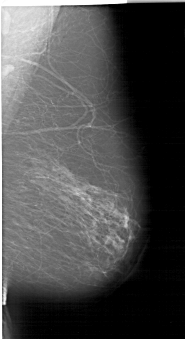

A_1192_1.LEFT_MLO

LEFT_MLO LINES 6856 PIXELS_PER_LINE 3856 BITS_PER_PIXEL 12 RESOLUTION 43.5 OVERLAY